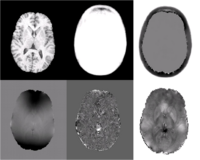

Quantifying magnetic susceptibility in the brain from the phase of the MR signal provides a non-invasive means for measuring the accumulation of iron believed to occur with aging and neurodegenerative disease. Phase observations from local susceptibility distributions, however, are corrupted by external biasfields, which may be identical to the sources of interest. Furthermore, limited observations of the phase makes the inversion ill-posed. We describe a variational approach to susceptibility estimation that incorporates a tissue-air atlas to resolve ambiguity in the forward model, while eliminating additional biasfields through application of the Laplacian. Results show qualitative improvement over two methods commonly used to infer underlying susceptibility values, and quantitative susceptibility estimates show better correlation with postmortem iron concentrations than competing methods.

We present a variational approach for Atlas-based Susceptibility Mapping

(ASM) that performs simultaneous susceptibility estimation and biasfield

removal using the Laplacian operator and a tissue-air susceptibility atlas. In [7,

8, 6] it was shown that applying the Laplacian to the observed field eliminates

non-local biasfields due to mis-set shims and remote susceptibility

distributions (ie. the neck/chest).

In this method, large deviations from the susceptibility atlas are penalized,

discouraging the estimation of artifactual susceptibility eigenfunctions in regions near

tissue-air boundaries where the Laplacian may not be sufficient to eliminate the

contribution of non-local sources and substantial signal loss corrupts the observed field.

Agreement of predicted and observed fields

within the brain is also enforced, but deviations in estimated susceptibility values outside the

brain are not penalized, allowing values at the boundary to vary from

the atlas-based prior to account for unmodeled external field sources (ie. shims).